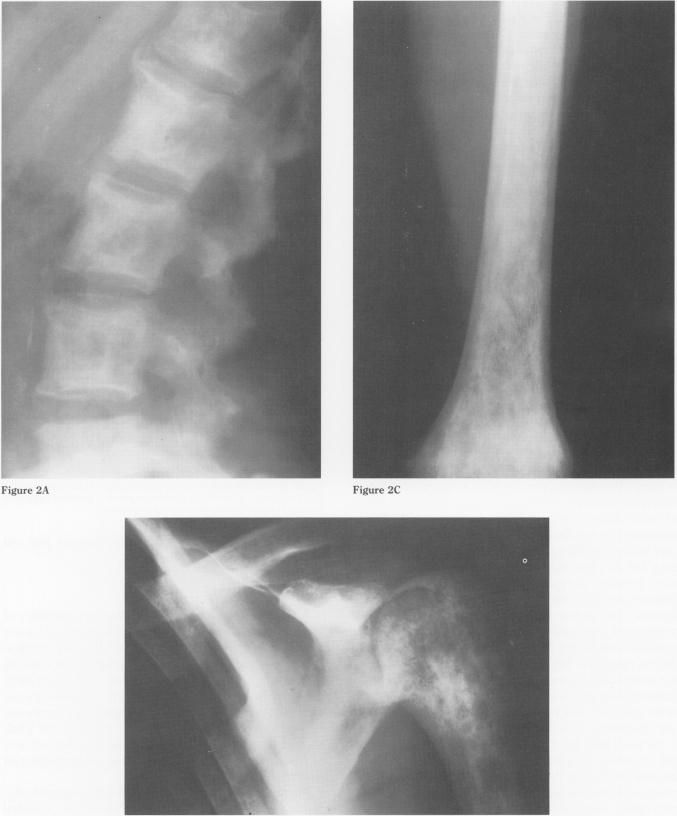

Mastocytosis is a rare disease of mast-cell proliferation with involvement of the reticuloendothelial systems including skin, bone, gastrointestinal tract, liver, lungs, spleen, and lymph nodes. Systemic mastocytosis is characterized by a combination of symptoms that relate to the mast cells' release of vasoactive substances, such as histamine. These symptoms include urticaria pigmentosa, flushing, syncope with hypotension, headaches, nausea, vomiting, diarrhea, and occasional bronchospasm. The diagnosis of mastocytosis is typically based on the presence of the characteristic extraosseus manifestations. A well recognized roentgenographic feature seen in 70-75% of patients with mastocytosis is diffuse osteolysis and osteosclerosis, affecting primarily the axial skeleton and the ends of the long bones. Rarely, the bony involvement consists of generalized osteoporosis, which may lead to pathologic fracture, or solitary lesions (mastocytomas) which may cause symptoms of localized pain. Four patients with previously diagnosed systemic mastocytosis had unusual skeletal lesions. Clinical and laboratory evaluation of these patients eventually led to the correct diagnosis of systemic mastocytosis. We report these four cases to emphasize the need for thorough evaluation of unusual musculoskeletal findings in association with extraosseus symptoms that are characteristic of mastocytosis. Knowledge of a wide differential diagnosis of unusual skeletal lesions should include systemic mastosytosis.

肥大细胞增多症是一种罕见的肥大细胞增殖性疾病,累及包括皮肤、骨骼、胃肠道、肝脏、肺、脾脏和淋巴结在内的网状内皮系统。系统性肥大细胞增多症的特征是一系列与肥大细胞释放血管活性物质(如组胺)相关的症状。这些症状包括色素性荨麻疹、潮红、伴有低血压的晕厥、头痛、恶心、呕吐、腹泻以及偶尔的支气管痉挛。肥大细胞增多症的诊断通常基于特征性的骨外表现。在70% - 75%的肥大细胞增多症患者中可见一种公认的X线特征,即弥漫性骨质溶解和骨质硬化,主要影响中轴骨骼和长骨末端。极少情况下,骨骼受累表现为全身性骨质疏松,可导致病理性骨折,或孤立性病变(肥大细胞瘤),可引起局部疼痛症状。4例先前诊断为系统性肥大细胞增多症的患者有不寻常的骨骼病变。对这些患者的临床和实验室评估最终得出了系统性肥大细胞增多症的正确诊断。我们报告这4例病例,以强调对于伴有肥大细胞增多症特征性骨外症状的不寻常肌肉骨骼表现进行全面评估的必要性。对不寻常骨骼病变进行广泛鉴别诊断的知识应包括系统性肥大细胞增多症。